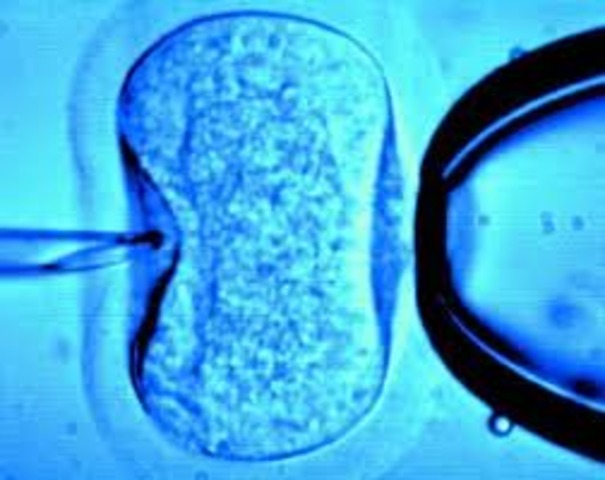

• In vitro

In vitro

Louise Joy Brown was born, the first human baby resulting from in vitro fertilization, in which sperm and egg are joined in a petri dish. The fertilized egg is later implanted in a womb.